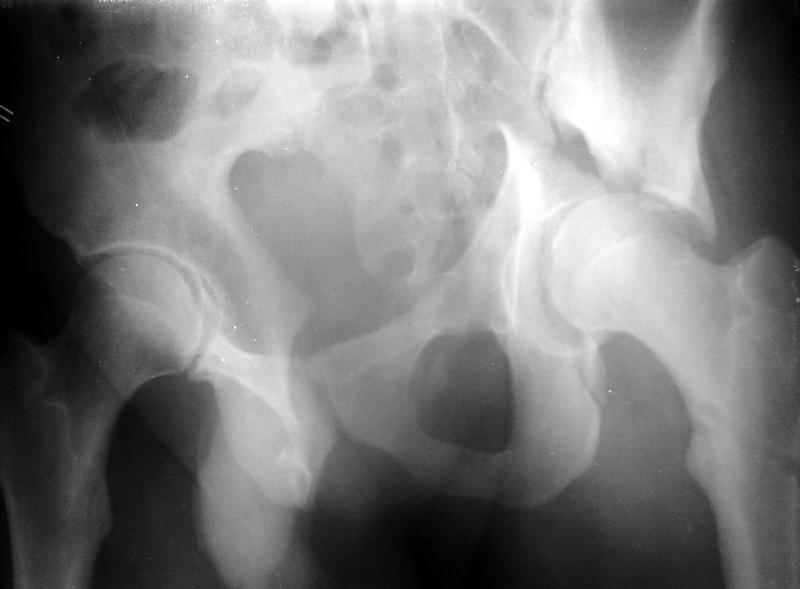

Сегодня на приеме был пациент, чьи начальный снимок напомнил обсуждаемый сейчас (см. выше). Снимки в других проекциях, показывающие истинный характер повреждения, ниже. Это inlet проекция (вход в таз) и запирательная проекция Judet.

1

2